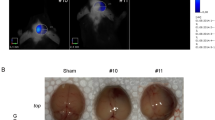

Silver, D.J., Siebzehnrubl, F.A., Schildts, M.J., Yachnis, A.T., Smith, G.M., Smith, A.A., Scheffler, B., Reynolds, B.A., Silver, J., Steindler, D.A.: Chondroitin sulfate proteoglycans potently inhibit invasion and serve as a central organizer of the brain tumor microenvironment. J. Neurosci. 33(39), 15603–15617 (2013)

ECM density [CSPG (\(E^*\)), Tumor ECM (\(\rho ^*\))] In a study of cell infiltration in glioma, Silver et al. [109] investigated the role of various CSPG concentrations (0–500 \(\upmu \mathrm{g}/\mathrm{ml}\)) and laminin concentration (5 \(\upmu \mathrm{g}/\mathrm{ml}\)) in regulation of glioma infiltration using both invasive and non-invasive co-culture assays. They found that while high concentrations of CSPGs (250, 500 \(\upmu \mathrm{g}/\mathrm{ml}\)) induce non-invasive glioma with astrocytes on the periphery of the well-defined tumor core, low levels of CSPG (0–10 \(\upmu \mathrm{g}/\mathrm{ml}\)) can allow glioma cell infiltration in the presence of astrocytes in the tumor aggregates [109]. It was shown that Cat-301 CNS CSPG with high molecular weight from brain in the density of 1.4 g/ml [38] can have similar biological properties as aggrecan, CSPG with the high molecular weight from cartilage in the density of 1.35–1.4 g/ml [53]. Dutt et al. [31, 32] investigated effects of versican, one of major CSPG components isolated from human glioma cell line (U251MG) and others (0–100 \(\upmu \mathrm{g}/\mathrm{ml}\)), on neural crest cell migration. They found that low concentrations of version V0/V1 (\(\sim \)25 \(\upmu \mathrm{g}/\mathrm{ml}\)) can block active migration of neural crest stem cells [31, 32]. The expression level of noncleaved isoform of Brevican/BEHAB was \(>\)4-fold higher in human gliomas compared to normal brain tissue [127]. Isolated versican levels in brain tissue were estimated to be 3 mg/100 g wet tissue components [9]. Glial HA-binding protein (GHAP) usually localized in white matter is present in the concentration of 8.2 mg/100 g in human white matter [9]. We take \(E^*=250\,\upmu \mathrm{g}/\mathrm{cm}^3\) from [109]. In a OV spread study [72], the tumor ECM concentration was estimated to be \(1.0\,\mathrm{mg}/\mathrm{cm}^3\) based on the experimental observation in the brain [63, 71, 112]. We take \(\rho ^*=1.0\,\mathrm{mg}/\mathrm{cm}^3\) from [72].